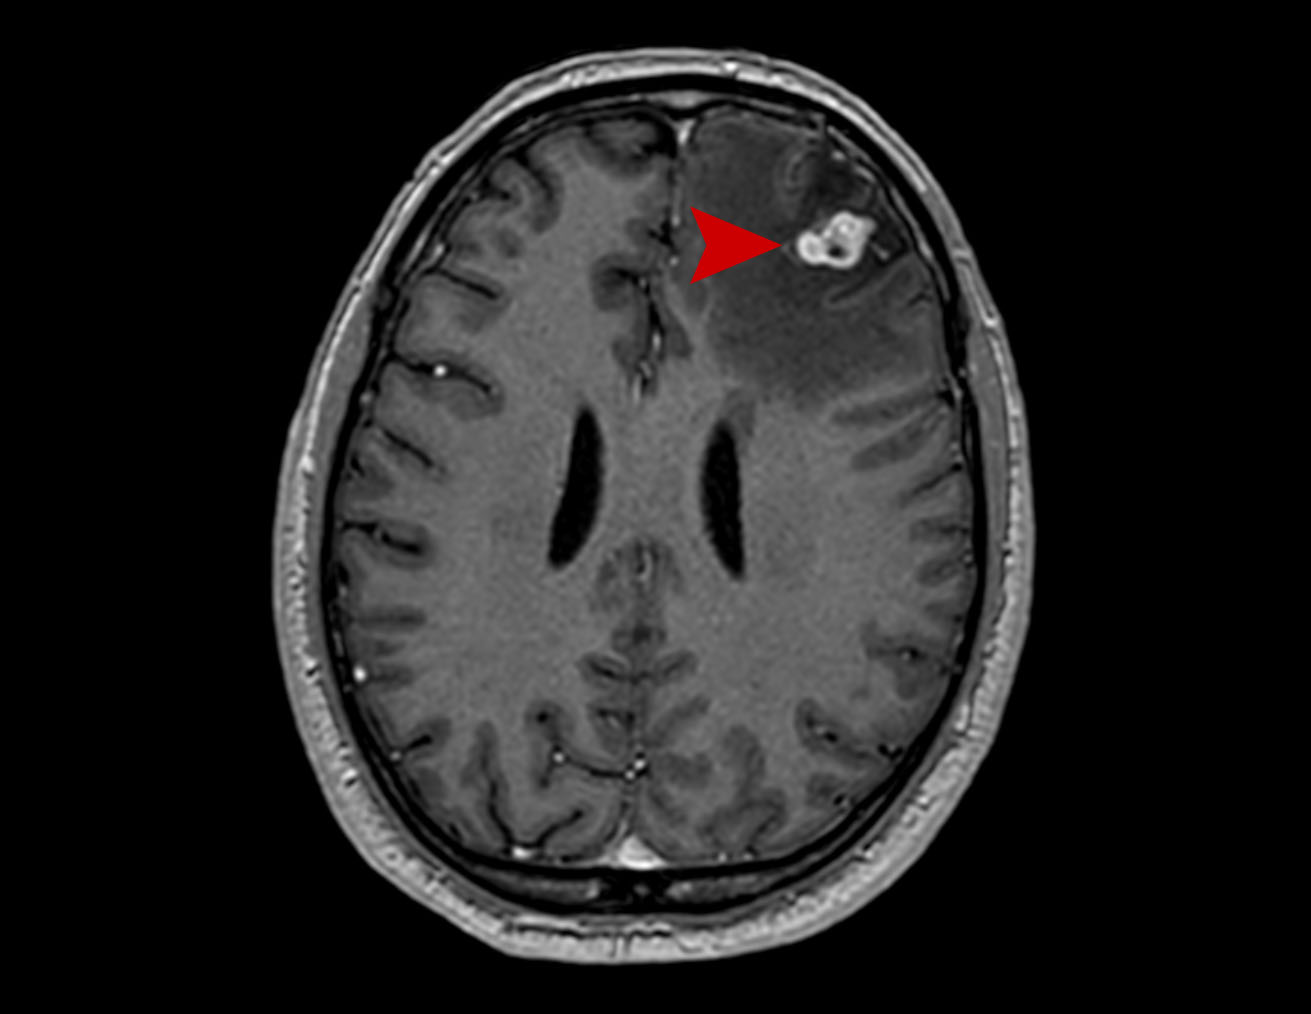

Μετάσταση Καρκίνος Πνεύμονα Θεραπεία με CyberKnife #15

Άρρεν 54 ετών με εγκεφαλική μετάσταση από Ca πνεύμονα αριστερά μετωπιαία. Σύγκριση MRI 5/2021 με…